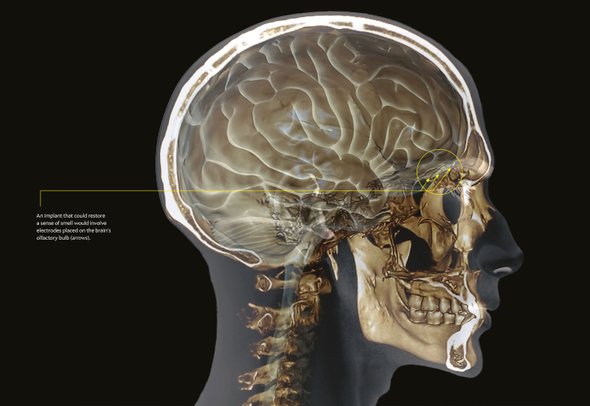

近日,来自美国弗吉尼亚联邦大学医学院及哈佛医学院的科学家们正在寻找能够刺激大脑嗅球及激发嗅觉的捷径,进而研发一个类似于人工植入耳蜗的电子设备,帮助嗅觉缺失患者恢复嗅觉。科学家们计划将该设备安装在鼻子的下方或眼镜上,包含一个气味感受器、外部微处理器,以及一个能够刺激嗅球不同区域的内部元件,可将化学气味转化为可用的电信号。目前存在的帮助嗅觉恢复的治疗措施的治疗效果均非常有限,该设备的成功研发及应用将有望帮助嗅觉缺失的患者成功恢复嗅觉。